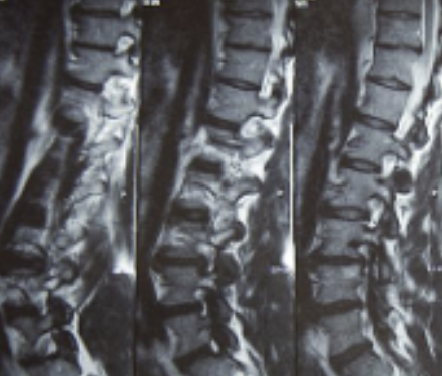

허리디스크를 정확하게 진단하기 위해서는 엑스레이로는 힘들며, MRI를 통해 검사해야 정확하게 볼 수 있습니다.

MRI가 몸에 좋지 않지만 허리 통증으로 엑스레이만 진행할 경우 오진이 많아 지속적인 통증이 계속된다면 허리디스크를 의심하고 MRI 검사를 한번 받아보시길 권유드립니다.